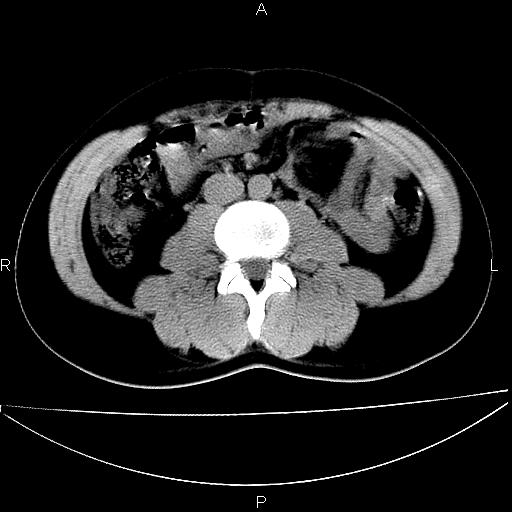

男 25岁 自述 尿频尿急,排尿困难20多天.无腰痛, b超说左肾盂轻度积水,左输尿管上端扩张.未见结石影. ct我看双侧肾盂轻度积水,双输尿管上端都扩张,大家看看能看见结石吗?

双肾轻度积水,双侧输尿管上段扩张(原因待查)。

双输尿管扩张下端未见高密度结石和输尿管晕轮征,不好说是结石.增强后如何?

双肾轻度积水,未见明确结石,薄层对结石检出率较高。

双肾盂及双输尿上段轻度积水,双输尿管未见明显结石影。